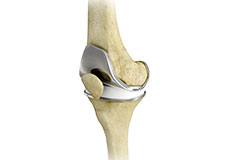

Unicondylar knee Replacement

Unicompartmental knee replacement is a minimally invasive surgery in which only the damaged compartment of the knee is replaced with an implant. It is also called a partial knee replacement.